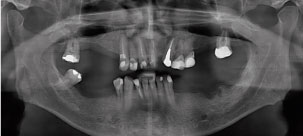

A 52-year-old man presented at the Oral Implant Dentistry Department of the Faculty Ilapeo, Curitiba, Brazil. The same complained of generalized mobility in the lower teeth. At the first moment, anamnesis and radiographic examination were performed. At the time of the clinical and radiographic examination was noted the presence of periodontal disease with points of exacerbation, generalized bone loss and mobility grade 2 in teeth (Figure 1 and Figure 2). It was suggested the extraction of the inferior dental elements for placement of dental implants and installation of a denture about implants with immediate loading.

Figure 1: Clinical image showing the initial oral condition of the patient. View Figure 1

Figure 2: Preoperative panoramic radiography. View Figure 2